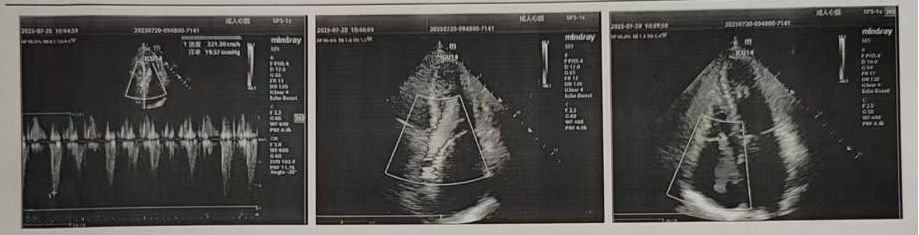

術(shù)前超聲